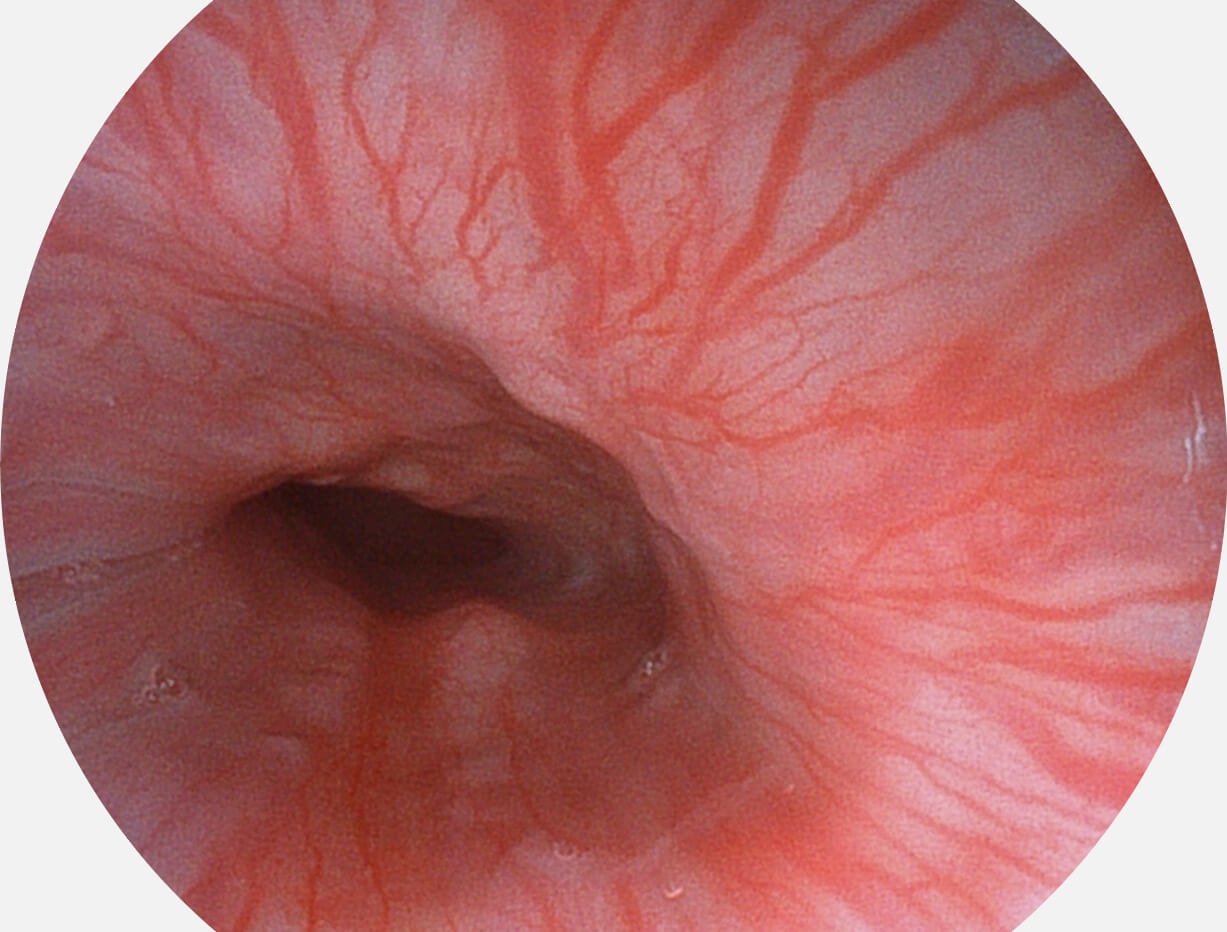

图像具有高亮度、高黏膜血管颜色对比度的特点,且不改变粘液、食物残渣、粪便的基本颜色,可在中远景下进行观察,助力消化道早期疾病的诊断。

SFI图像

白光图像